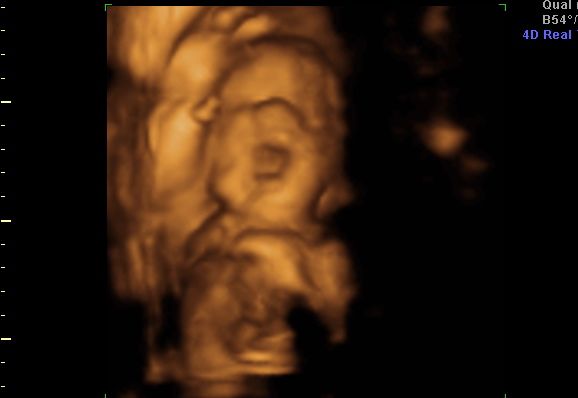

Both of our little ones are doing great. Lil P is talking more and more each day, with her newest phrase being "wuv you". She's very independent in so many ways, but loves to cuddle with the Knight and I any chance she gets. Yesterday I bought her a new "big girl" bedroom set that consists of a twin size bed....yup, it'll be bye bye crib in a few short weeks. Squirt is moving quite often and seems to be developing right on target. I go to my next OB appointment on Wednesday, so more updates very soon. We are officially 8 weeks and 4 days away from delivery...Yikes & Yippie!!!